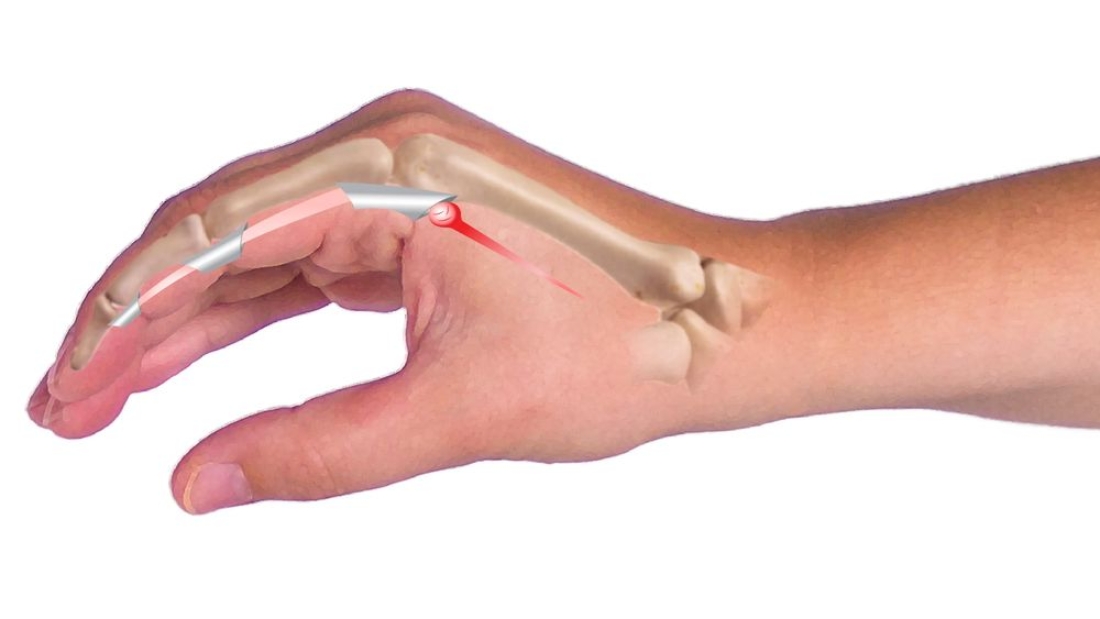

هي حالة مؤلمة وانغلاق في الأصابع نتيجة التهاب أوتار الأصابع وأغماد الأوتار. اصبع الزناد وتحدث المشكلة الصحية خاصة عند ثني الإصبع أو تقويمه. يمكن قفل الإصبع كما لو كان يقوم بحركة "الزناد".

ويتميز بالتهاب وتورم الأوتار التي تسمح للأصابع بالانحناء. يؤدي هذا إلى ضغط الوتر في منطقة انتقالية ضيقة في غمد الوتر.

- اصبع الزناد يتجلى بشكل بارز مع الألم. يتم الشعور بهذا الألم في قاعدة الإصبع، وعادة في راحة اليد. قد يزداد الألم مع ثني الإصبع وتمديده.

- وهو من أكثر الأعراض المميزة. قد ينغلق الإصبع عند ثنيه أو تمديده. قد ينتهي هذا القفل بصوت أو إحساس "نقر" عند تحريك الإصبع. قد يصبح الإصبع منحنيًا أو مغلقًا في الوضع المفتوح وقد يحتاج إلى تقويمه يدويًا.